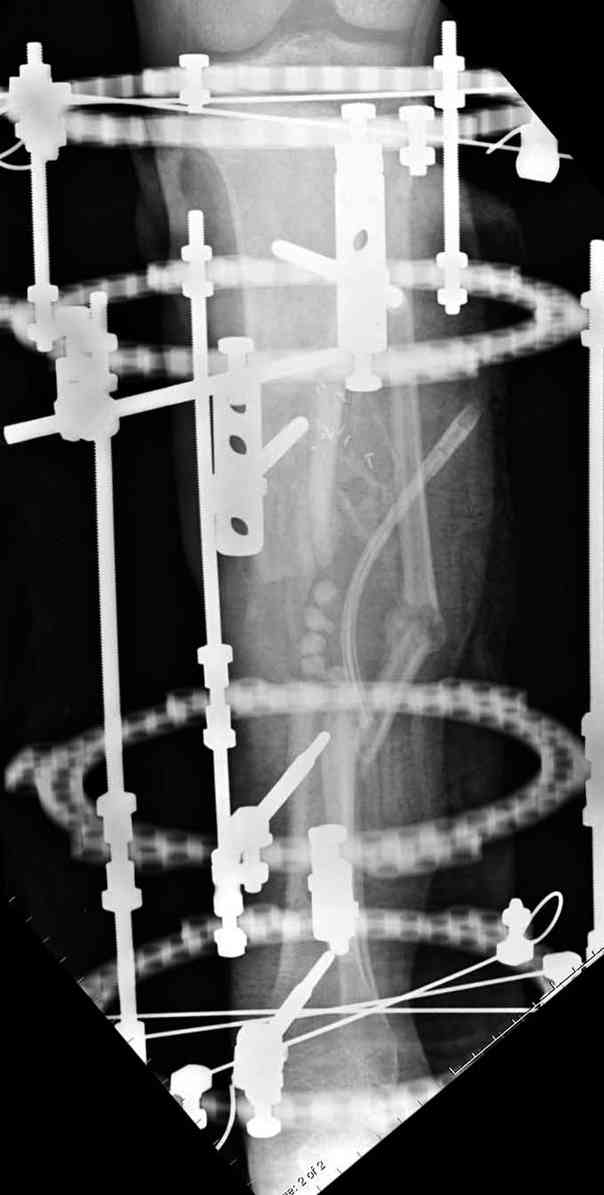

Согласен с тобой, короткий дистальный фрагмент, нет места ни для штифта, ни Т-образной пластины, да и шурупы мешают.

Конечно, возможность костной пластики не снимается, хотя из-за огромного дефекта имеется опасность плохого приживления, поэтому рекомендую приподнять блокированную мышечную пластику,

сделать поперечную остеотомию диафиза, полость заполнить antibiotic beads и начать удлинение.

Из аппаратов предпочтительно циркулярный, на дистальном фрагменте можно увеличить количество спиц.

Интересный случай, надо стараться сохранить сустав, любые осложнения грозят потерей части движений в суставе. При ведении сложных околосуставных дефектов не мешает предварительная моральная подготовка пациента к артродезу.

Здесь случай, хотя не тот уровень, но принцип "удлинения после заполнения дефекта Antibiotic Beads" сохранен, можно немного увеличить количество бус.